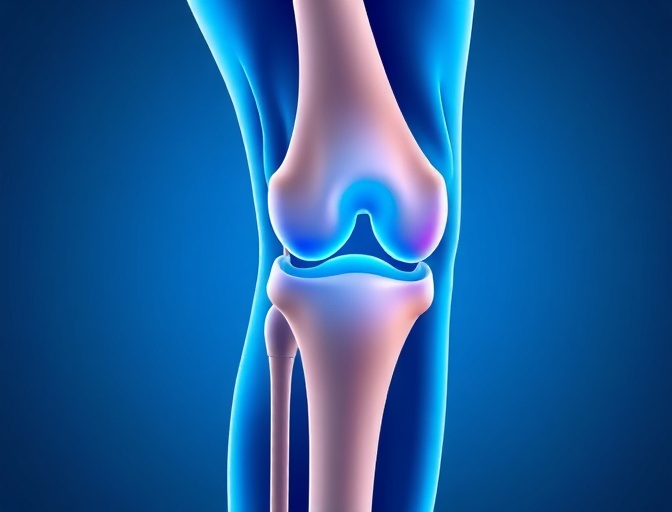

Knee Replacement

State-of-the-art total and partial knee replacement procedures that restore mobility and eliminate pain using the latest implant technology.

Knee Replacement Outcomes

Our knee replacement patients experience significant improvement in pain relief and functional ability, with 95% reporting excellent or good results.